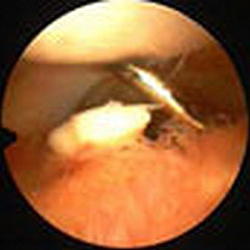

Если данных рентгенографии по каким-то причинам недостаточно для определения тактики дальнейшего лечения, пациентов направляют на КТ плечевого сустава. Для того чтобы получить представление о состоянии мягкотканных структур, выполняют МРТ плечевого сустава. При необходимости осуществляют контрастную артрографию. Если есть возможность и соответствующие показания, проводят диагностическую артроскопию, позволяющую детально изучить сустав изнутри при помощи специальной камеры.

Операция Банкарта может проводиться как классическим способом (через обычный разрез), так и с использованием артроскопического оборудования. В последнем случае в области сустава делают два небольших разреза длиной 1-2 см., через разрезы вводят артроскоп и манипуляторы, после чего под контролем зрения выполняют все необходимые элементы хирургического вмешательства. Использование артроскопической техники позволяет существенно снизить травматичность операции, минимизировать риск развития осложнений и сократить срок реабилитации пациента. В настоящее время эта методика становится золотым стандартом при лечении привычных вывихов плеча.